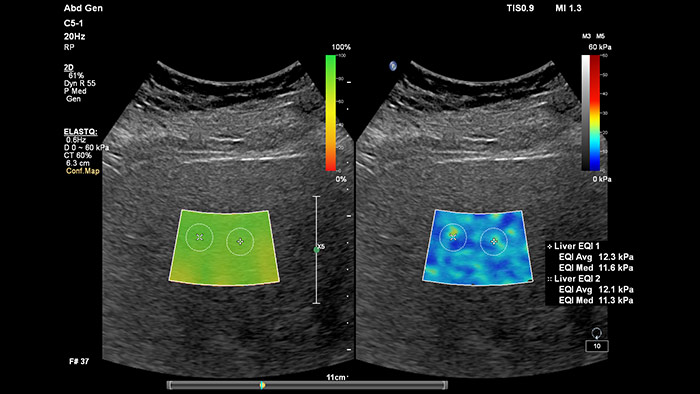

A elastografia por ondas transversais ecográficas proporciona um método não invasivo, reprodutível e de fácil aplicação para a avaliação da rigidez dos tecidos. Investigações sugerem que, em vez de um procedimento de biópsia dispendioso e doloroso, uma simples ultrassom com elastografia por ondas transversais pode tornar-se rotina na avaliação do estado de doenças hepáticas. A elastografia por ondas transversais de alto desempenho do ElastQ Imaging inclui a avaliação quantitativa codificada por cores através de regiões de interesse (ROI) em tempo real e de grandes dimensões da rigidez do tecido. O ElastQ Imaging também inclui a capacidade de efetuar medições retrospetivas nas imagens armazenadas e uma apresentação de mapa de confiança única utiliza a análise inteligente para acrescentar uma garantia adicional de que as medições do utilizador são obtidas em áreas de tecido com propagação adequada de ondas transversais.

A medição da rigidez do fígado é efetuada em segundos através de um simples exame não invasivo.